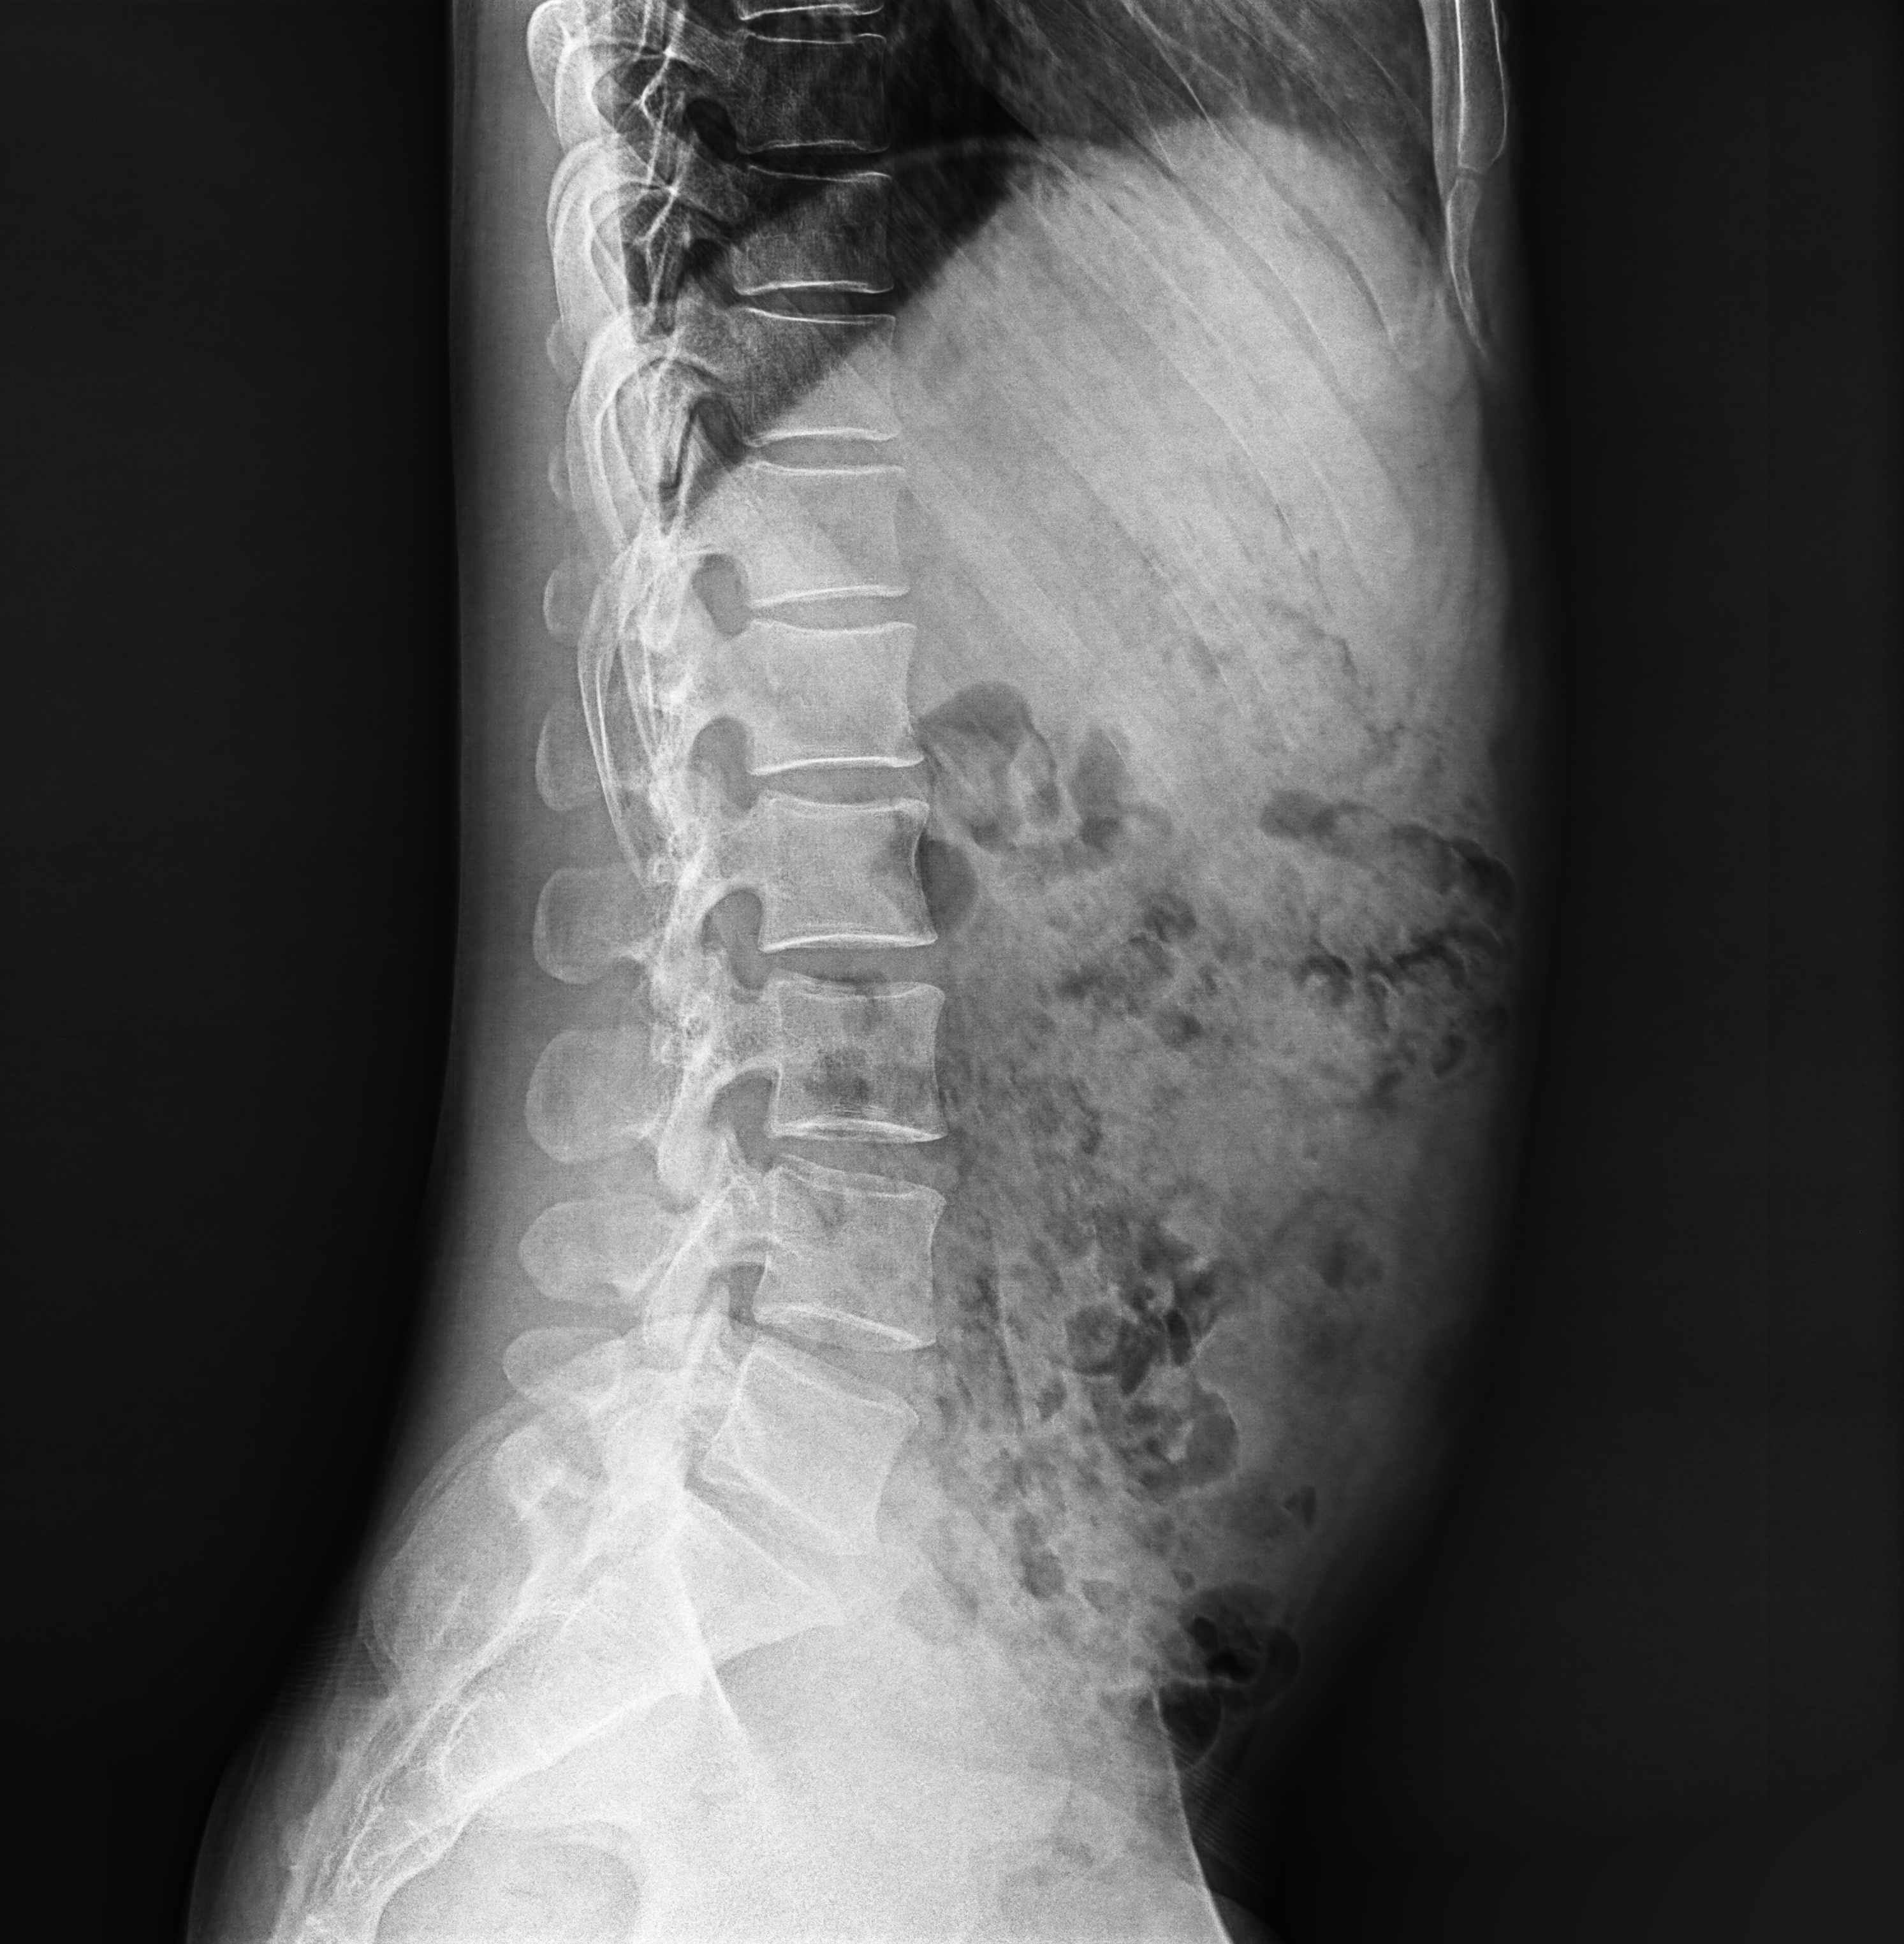

臨床圖片

腰